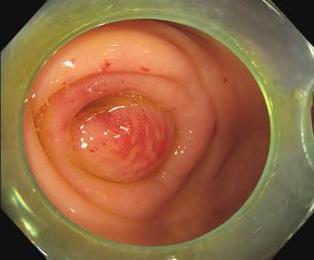

摘要:目的 比较环泊酚与丙泊酚对无痛胃镜检查患者咽部吞咽功能的影响。方法 选择2021年12月8日-2022年12月8日于该院行无痛胃镜检查的患者237例。采用随机数表法将患者分为丙泊酚组(P组,n = 121)和环泊酚组(C组,n = 116)。P组手控静脉注射丙泊酚剂量2.5 mg/kg,C组手控静脉注射环泊酚剂量0.6 mg/kg,推注时间 > 30 s。改良警觉/镇静评分量表(MOAA/S)评分 ≤ 1分时,行内镜检查。记录麻醉诱导前(T1)、胃镜通过口腔时(T2)、胃镜退出时(T3)、入麻醉恢复室(PACU)时(T4)和出PACU时(T5)的血流动力学指标[平均动脉压(MAP)和心率(HR)]、麻醉相关情况[检查时间、镇静药物总剂量、补充镇静药物剂量、苏醒时间和PACU停留时间]、吞咽功能[吞咽困难严重性评分(DSS)、渗透-误吸量表(PAS)评分、喉内收反射发生情况和环杓关节松弛情况]和不良反应发生情况(注射痛、体动、呼吸抑制、呼吸暂停、气道梗阻、心动过缓和术后头晕)。结果 C组重度吞咽功能障碍发生率为12.9%,明显低于P组的33.1%;C组PAS评分7和8分的占比为12.9%,明显低于P组的33.1%;C组喉内收反射消失率为37.1%,明显低于P组的56.2%;C组环杓关节松弛率为42.2%,明显低于P组的56.2%,差异均有统计学意义(P < 0.05)。两组患者不同时点血流动力学指标、检查时间、苏醒时间和PACU停留时间比较,差异均无统计学意义(P > 0.05)。C组镇静药物总剂量和补充镇静药物剂量明显少于P组,差异均有统计学意义(P < 0.05)。C组体动发生率为15.5%,明显低于P组的31.4%,C组呼吸暂停发生率为0.0%,明显低于P组的5.0%,C组注射痛发生率为5.2%,明显低于P组的66.9%,差异均有统计学意义(P < 0.05)。两组患者呼吸抑制、气道梗阻、心动过缓及术后头晕发生率比较,差异均无统计学意义(P > 0.05)。结论 在胃镜检查时,与单独使用丙泊酚相比,单独应用环泊酚,可能更有利于患者在镇静状态下,保留一定的吞咽功能,还能减少体动的发生,降低误吸的发生风险。值得应用于临床。